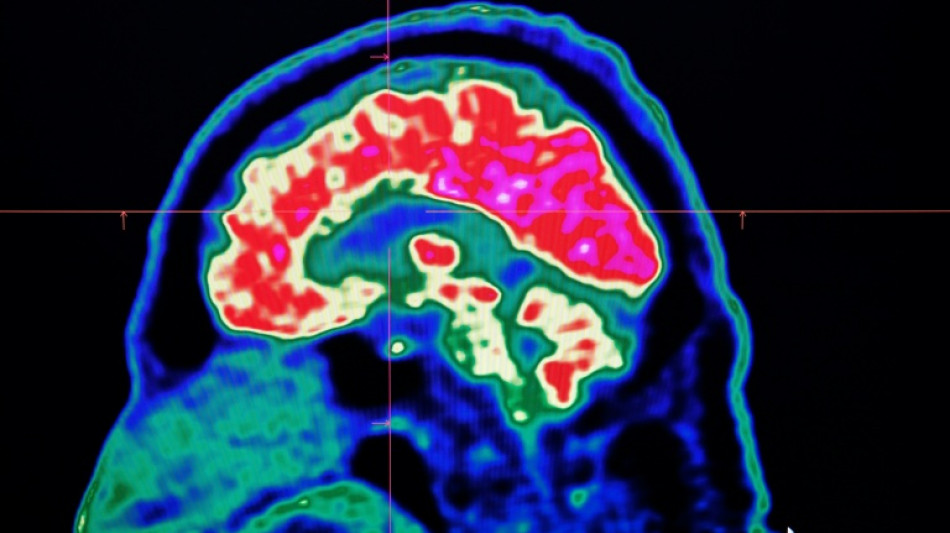

Final report casts doubt on existence of Canada mystery brain illness / Photo: © AFP

A Canadian medical report published Friday found no evidence linking environmental factors to an unusual set of neurological symptoms affecting hundreds of people, a five-year saga that has shaken a small Atlantic province.

In 2021, health officials in New Brunswick launched an investigation involving 48 patients with a range of neurological symptoms but no apparent common illness. These included muscle spasms, memory loss, hallucinations and balance issues.

Some in the province of less than a million people began describing the condition as a mystery brain disease.

Provincial officials said at the time that the patient group could be suffering from a new disease not previously seen in Canada and began using the term "possible neurological syndrome of unknown cause."